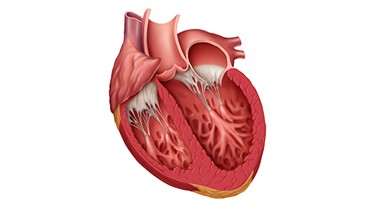

In 2025, cardiologists and cardiac surgeons at NewYork-Presbyterian led breakthroughs that impacted a range of diseases and conditions from advanced heart failure to pediatric valve disease. Physicians and researchers from Columbia and Weill Cornell Medicine pioneered the use of artificial intelligence to identify structural heart disease, launched a mobile app to expand access to heart failure education, performed one of the first split-root domino partial heart transplants, and more. Our experts remained at the forefront of innovative, multidisciplinary care, delivering comprehensive treatment for the most complex cardiac diseases.

Our world-renowned Columbia and Weill Cornell Medicine physicians and surgeons in our comprehensive cardiology, heart surgery, and vascular programs spearhead groundbreaking clinical and scientific research and provide the most innovative treatments to optimize patient outcomes for all stages of disease complexity. Our clinicians are experts in minimally invasive approaches and novel therapeutics for all types of heart disease and work across disciplines to provide compassionate care to all patients.